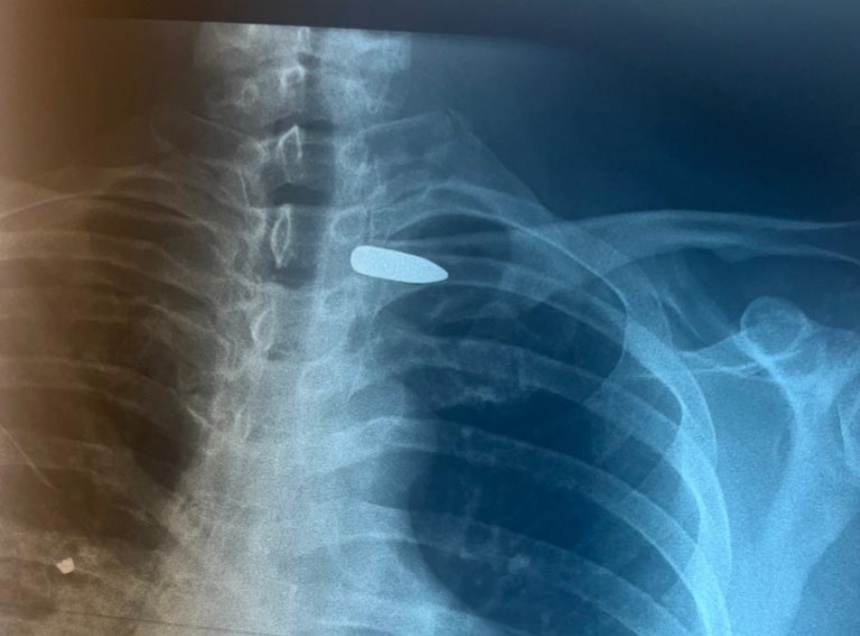

«Вследствие проникающего ранения в правую половину шеи пуля осталась в области сосудисто-нервного пучка в подключичной области слева», – рассказали в больнице и отметили, что мужчине потребовалась операция, в которой участвовал сосудистый хирург Абдулло Шабонов.

Пулю, находящуюся между ключицей и подключичными сосудами, извлекли. На данный момент состояние пациента оценивается как удовлетворительное.